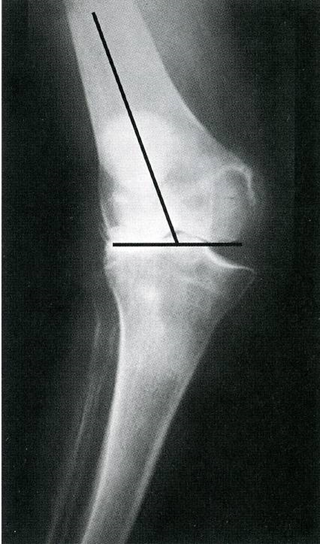

正确的下肢力线

正确的关节线和胫骨切骨量